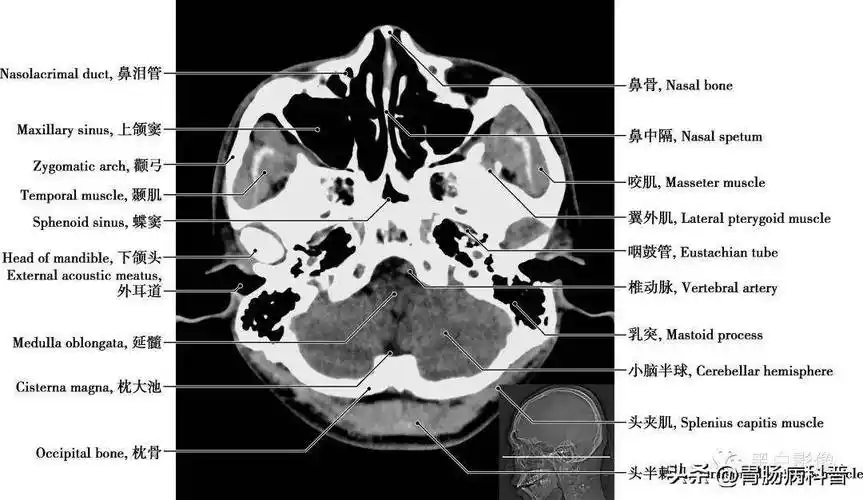

颅脑ct的正常解剖

详细标注版——颅脑ct正常解剖图谱_中央_小脑_纤维